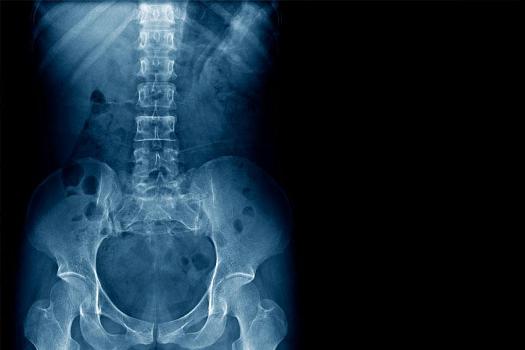

Наиболее распространённым вариантом исследования является обзорная урография. При такой методике специалист делает снимки почек, мочеточников и пузыря. На этих снимках есть возможность увидеть форму и расположение почек, а также часть поясничных мышц.

Выделяют также экскреторную процедуру, которая основана на выделительных способностях почек. В этом случае снимки делаются в тот момент, когда почки выделяют контрастное вещество. С помощью такого обследования можно выявить интенсивность заполнения мочевого пузыря жидкостью, форму и габариты камней, а также других обнаруженных новообразований.

В некоторых случаях назначается и внутривенная процедура. Пациенту с опорожнённым мочевым пузырем вводится контрастное вещество. Снимки делаются во время накопления почками этого вещества (сначала в первые две минуты, а потом с интервалом в несколько минут). С помощью этой методики можно увидеть состояние органов мочевыделительной системы, наличие опухолей, расширение полостей и так далее.